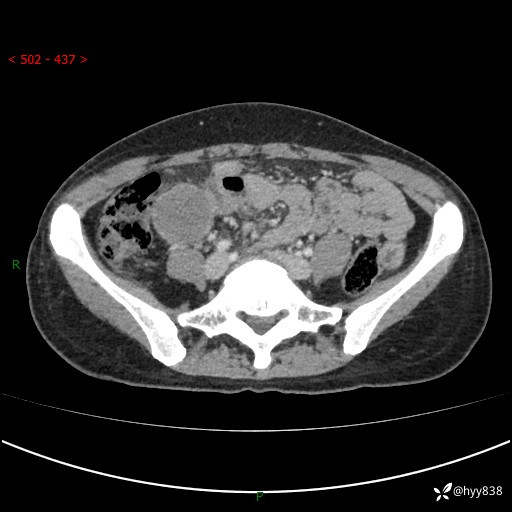

现病史:患者自诉于1周前无明显诱因出现剑突下间断性隐痛,尚可忍受,不向其它部位放射,无恶心呕吐、腹泻便秘等不适,于当地市第二人民医院就诊,行CT结果示:1.右中腹占位,间叶组织来源可能2.小肠梗阻3.盆腔积液4.腹腔积液5.副脾6.肝囊肿;于荆州二医行抗炎,抑酸,护胃,补液等对症支持治疗;患者病情好转,今为求进一步诊治,遂来我院门诊就诊,门诊以“腹腔肿瘤”收入院。 起病以来,患者精神、睡眠、饮食一般,大小便正常,近期体力体重无明显改变。

腹部CT增强(外院平扫)